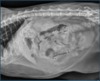

What is shown in these images?

A

canine acute gastric dilation

-pylorus is still in the normal place; right and more ventral

What are the imaging findings in acute gastric dilation?

-stomach is primarily gas distended

-stomach remains in normal position

-must recognize location of pylorus via right and left lateral views to evaluate